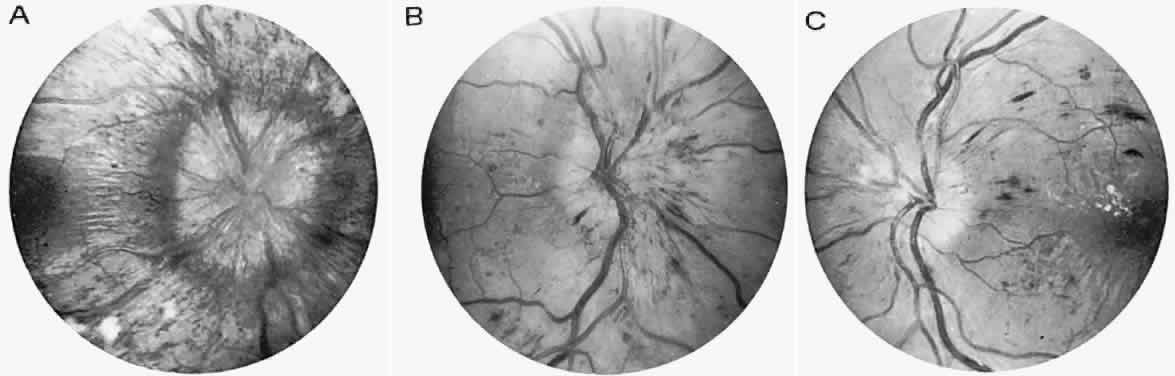

The retinal variety may be admixed in a person who suffers the more conventional attacks of migraine. It is presumed that vasospasm in the retinal circulation determines transient hypoxia, perhaps somewhat similar to the visual cortical event. On rare occasions, the fundus has been examined during typical retinal migraine episodes, and arterial constriction has been described. Wolter and Burchfield106 photographically documented such an episode and demonstrated mild “retinal edema”; vessel narrowing is also evident (Fig. 8). Fortunately, permanent complications of retinal migraine are rare. These may take the form of central retinal artery occlusion or ischemic papillopathy (see Volume 2, Chapter 16); nerve fiber bundle visual field defects may be demonstrated (Fig. 9).

Fig. 8. Retinal migraine. A. During amaurotic episode. Note the dusky appearance of the fundus, increased retinal sheen (possibly edema), and dark narrowed veins (arrows). The disc is also hyperemic. B. Fundus after episode. Compare paired arrows. (Courtesy of Dr. J. Reimer Wolter)

Fig. 9. An 18-year-old student with recurrent episodes of left retinal migraine. After a typical attack, he noted an inferior field defect. A. Fundus shows a defect in the superior arcuate nerve fiber bundle (between arrows: compare fiber layer below disc). B. Visual field defect corresponds to a retinal nerve fiber layer defect.